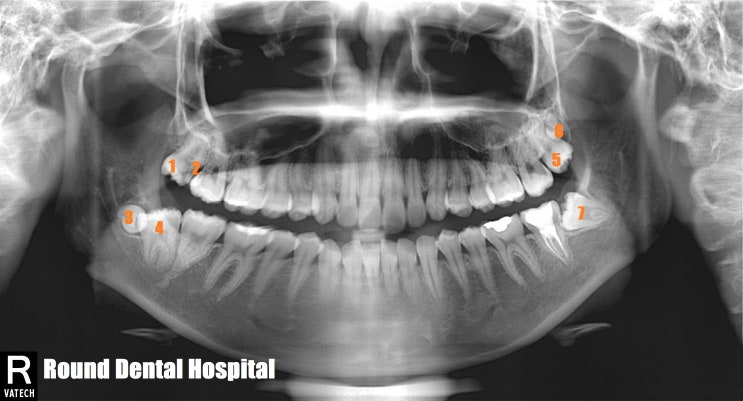

라운드치과병원 7개 사랑니 발치해 드리기

구강악안면외과 전문의가 진료하는 라운드치과병원입니다. 구강악안면외과 전문의는 임플란트 수술, 매복사...